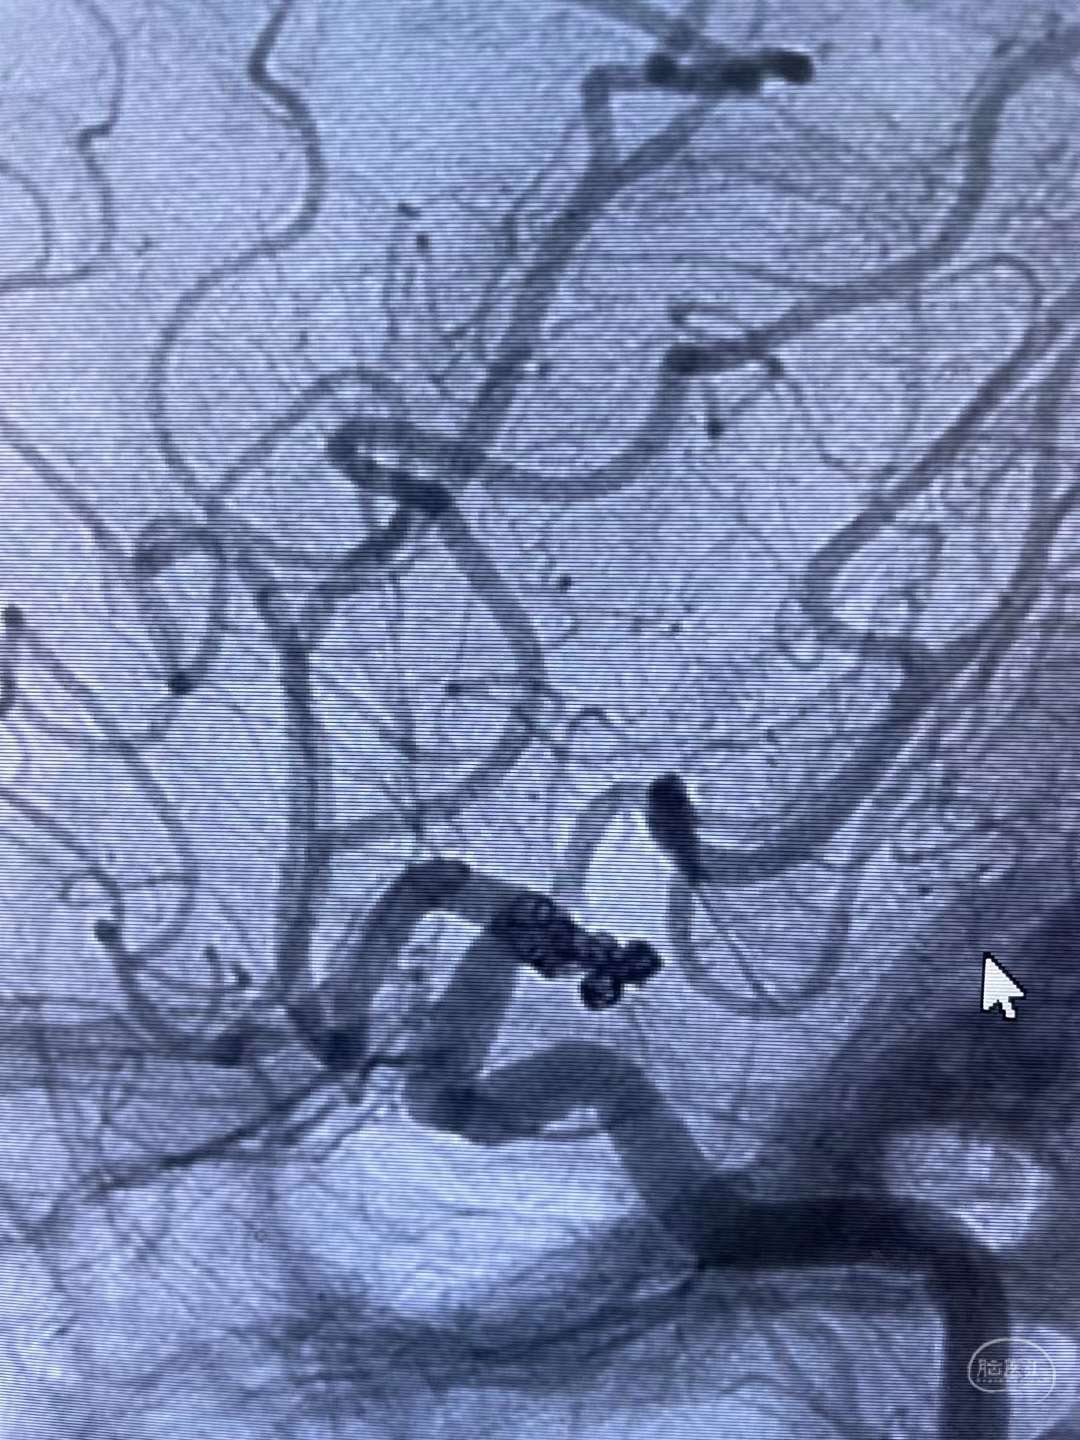

DSA提示右侧后交通分叶状动脉瘤

术中弹簧圈填塞分叶子瘤,为保护后交通动脉,瘤体选择疏松填塞